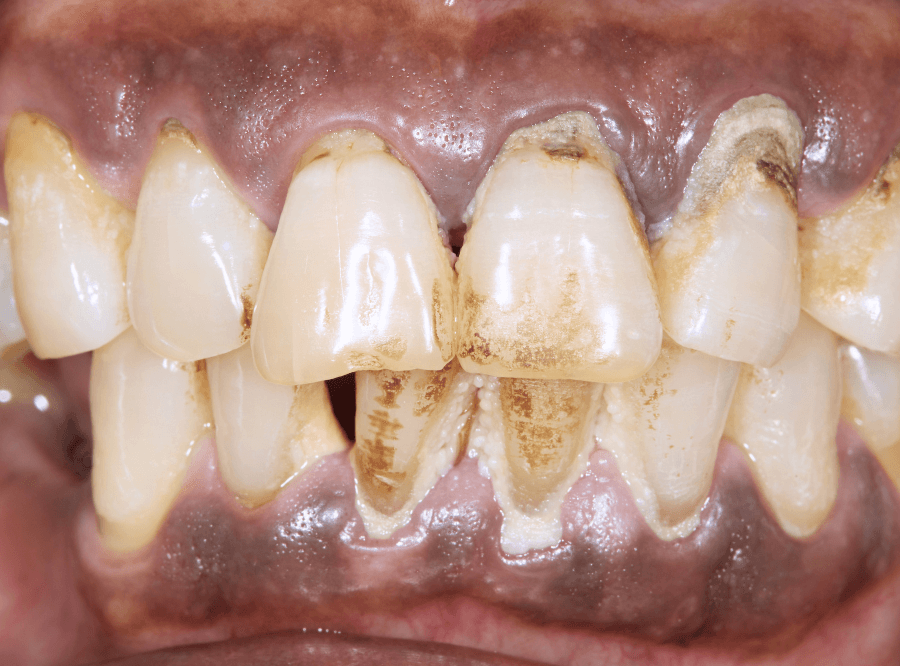

歯周病の主な症状

歯肉の腫れ・出血

歯周病の初期段階「歯肉炎」では、歯と歯の間や歯と歯ぐきの境目にプラーク(細菌のかたまり)がたまり、炎症を引き起こします。 その結果、歯肉が腫れ、わずかな刺激でも出血しやすくなります。

歯肉炎(しにくえん)《初期段階》

歯肉炎は、歯と歯ぐきの境目(歯周ポケット)にプラーク(歯垢)がたまることで、細菌が繁殖し、歯肉が炎症を起こし始めている状態で、ブラッシング時に出血します。

この段階なら、正しいブラッシングと歯周病治療で健康な歯肉に戻すことが可能です。

「ちょっと血が出るけど、痛くないから大丈夫♪」と放置しないことが大切です。

症状の目安

歯肉からの出血

治療

歯ブラシ指導、スケーリング

軽度〜中等度の歯周炎

歯周炎は、歯肉炎が進行して歯を支える骨(歯槽骨)や歯根膜まで炎症が波及した状態です。

歯肉の腫れが原著になり、歯が揺れる、口臭を指摘される事もあります。

軽度~中等度の段階であれば、適切な治療で進行を食い止めることが可能ですが、放っておくと歯を支える骨(歯槽骨)がどんどん壊されていきます。

治療は、スケーリングに加え、スケーリング・ルートプレーニングという、歯や歯根の表面の歯垢・歯石を除去する処置を行います。

古いつめ物やさし歯は、歯周病の改善の妨げになるため、やりかえます。

進行具合が大きい場合、さらに歯肉の切除や歯肉を開いて歯石を除去する「歯周外科」が必要になります。

歯肉の腫れ、歯の揺れ、口臭

歯ブラシ指導~SRPが中心

重度の歯周炎

重度歯周病は、歯を支えている骨が深くまで溶かされ、歯がグラグラと動く、最悪の場合は自然に抜け落ちてしまうような状態です。

歯周病菌がお口の中から、全身の健康にも影響を及ぼす危険性があります。

重度まで進行すると、歯を保存するのが難しくなってくる段階です。

治療は外科処置もしくは抜歯が中心になります。

激しい歯肉の腫れ、歯の揺れ、口臭、噛めない

歯周外科、抜歯